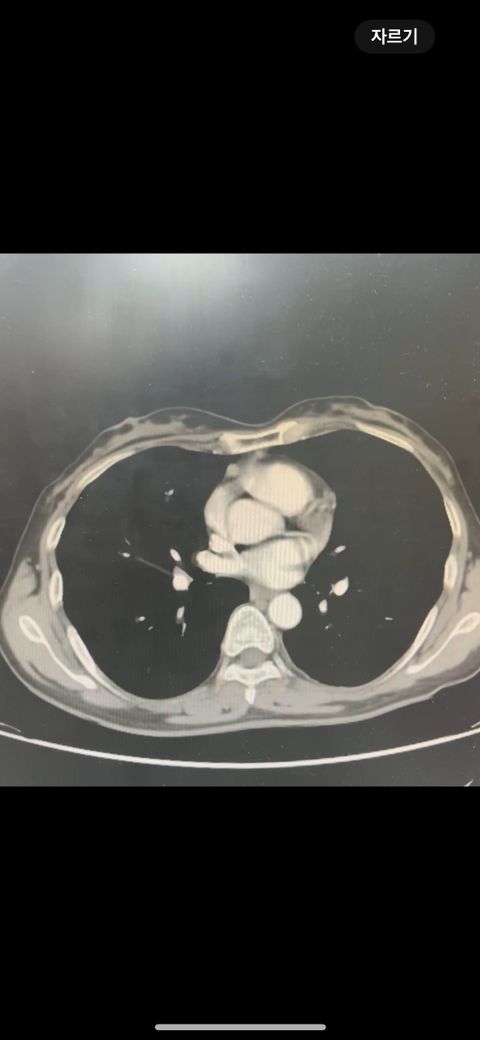

복부 ct 판독 부탁드립니다 (contrast)

결과는 3일 뒤 보긴 하는데 우선 영상만 있는 상태라 영상 캡쳐 한 거 대략적으로라도 확인해주실 수 있나요.. !!!!!!!!!!

• 2번 째 사진

*** 먼저 답변드리기에 앞서 상기 질문에 대한 답변은 굉장히 제한된 답변이고, 경우에 따라 틀린 답변이 될 수 있습니다. CT의 경우 단면을 연속적으로 봐야 의학적인 설명이 가능하기 때문에 일부 사진만으로는 해석이 어려울 수 있습니다.

위 사진에서는 비장비대의 가능성과 자궁쪽으로 혹이 일부 보이는 소견이 의심되나, 정확한 판독은 3일 뒤에 받아보시는 것이 도움이 될 수 있겠습니다.